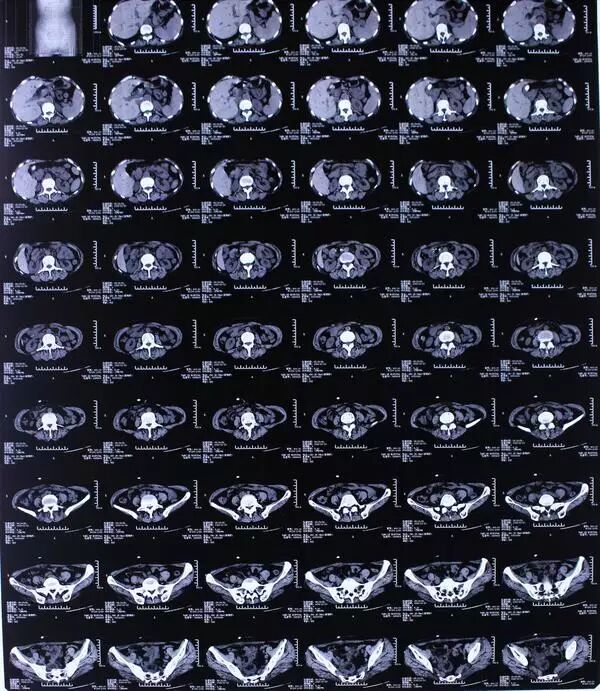

当地医院妇科以盆腔肿物拟行手术治疗,术中探查发现肿物侵及骶尾骨,无法完全切除,遂转诊于西安某大型综合性三甲医院行盆腔CT示:骶前、盆腔右侧见团块状混杂密度影,大小约9.1*7.3cm,右侧骶孔扩大,考虑神经鞘瘤可能性大。复查MRI也支持上述观点。

影像资料

术后影像